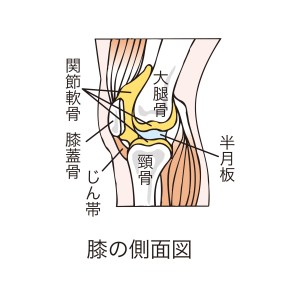

「関節のこの部分、脛骨顆部と脾骨顆部、つまり関節同士がお見合いをしている部分が上下両方ともつぶれています。」

「そして、この脾骨の上にダラーっとしているものがあるでしょう。これは前十字靱帯というのですが完全に切れて落ちています。完全に先っぽがあるのが見えるでしょう。靱帯が骨にくっついていたら先っぽは見えないからね。そして、膝を触診した時に、左外側に簡単に足が曲がっていきます。ほら、反対の足は外側には動かないのにこっちの足はこんなに反るでしょう?」

「これは側副靱帯といいますが、ここが正常な状態よりもかなり伸びています。戻りがなくなったゴムのような状態です。膝の横を支えるものと前に落ちないようにするものがなくなっている状態です。」